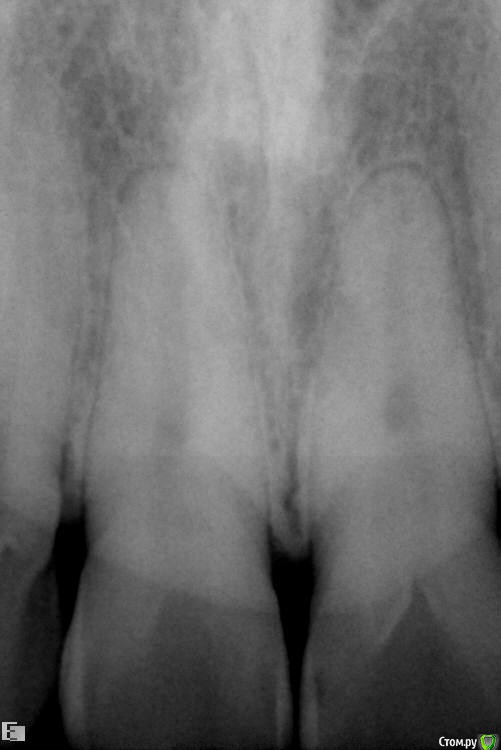

VladV Опубликовано 19 апреля, 2015 Поделиться Опубликовано 19 апреля, 2015 Помогите, пожалуйста, советом. Заранее извиняюсь за простыню. Около полутора месяцев назад пропустил два удара в голову. Один пришелся в верхнюю челюсть, другой в районе правой брови. Была сильно разбита верхняя губа, которая слиплась и срослась сама (не зашивали). Зубы, вроде бы, не беспокоили. Проверял холодом - реакция есть. Явных болевых ощущений не было, но как-то стал чувствовать верхнюю единицу (11), иногда совсем чуть-чуть зуб поднывал и было ощущение, что совсем немного сдвинулся назад, внутрь рта (возможно, всегда таким был, не обращал внимания). При смыкании зубов поверхностью верхнего к поверхности нижнего, а не нижний за верхний, явной боли не было, но я старался не смыкать лишний раз и не кусать этими зубами. Губа зажила где-то через две недели, только внутри уплотнение небольшое осталось. Не знаю, важно ли, но примерно после заживления губы то ли словил вирус, то ли есть связь с зубами, но начался сильный насморк, который длился недели две и вторая неделя была с густыми зелеными (простите за подробности) выделениями и даже иногда кровь шла из носа от попыток их вымыть и высморкать.Спустя месяц, когда насморк прошел, решил сходить к стоматологу в частную клинику и проверить зубы на всякий случай, т.к. непонятные ощущения в 11 зубе остались. Простучали зубы 22-21-11-12. У всех зубов чувствительность одинаковая, у 11 чуть сильнее. Сделали несколько прицельных снимков. Врач ничего криминального с корнями не обнаружил. Посоветовали сделать чистку зубов ультразвуком и AirFlow, т.к. был сильный налет и отложение камня.Через пару дней сделал чистку. Полтора часа чистили все зубы, так как около 5 лет до этого не чистил. Врач долго не мог понять, что за смолянистый темный налет был на зубах (не курю и кофем не злоупотребляю), в итоге выяснили, что из-за постоянного полоскания ротовыми ополаскивателями, содержащими хлор. Увлекался ими последние полгода. После травмы зуба казалось, что после ополаскивания зубу легче становилось и его долго ничего не беспокоило. Во время осмотра между верхними единицами обнаружился легкий кариес. Врач сказал, что на корни и мои ощущения 11 зуба он никак влиять не может. После чистки местами были травмированы десны, местами маленькие гематомы были, некоторые зубы стали особенно чувствительно переносить холодное и горячее. Но то ли так совпало, то ли из-за чистки, 11 зуб стал чаще поднывать, причем, непонятные ощущения переместились ближе к пространству между 11 и 12 зубом, и на 12 зуб вроде бы тоже стали распространяться. Сложно описать, но такое ощущение, что чувствительность куда-то ближе к носу ушла, иногда как будто напряжение какое-то между зубами возникало, будто еда застряла. Стал непроизвольно тсыкать - прислонять язык к щели 11-12, 11-21, 12-13 и втягивать резко воздух, так легче что ли становилось или из-за ощущений от увеличенных просветов между зубами. Потом то ли из-за того, что не пользуюсь передними зубами, то ли из-за чего-то другого, но появилось ощущение, что изменился прикус. Нижние единицы стали как-то ощутимее упираться в верхние единицы, будто в другом месте из-за якобы ушедшей чуть-чуть вперед нижней челюсти. Иногда верхние единицы становились как чужие, снижалась чувствительность что ли. Иногда кажется соленоватый привкус у десны между 11 и 12 зубами, хотя крови и каких-либо выделений в слюне нет. В какие-то дни эти ощущения уходили, в какие-то возвращались. Заметил, что у 11 зуба есть небольшая подвижность, определил прислоняя палец к щели 11-12 и сжимая/расслабляя челюсти. Понаблюдав неделю пошел уже в другую частную клинику. Там опять сделали снимки (прилагаю к сообщению), опять ничего криминального не обнаружили. Кариес легкий между 11 и 21 видят, рекомендуют убрать и отреставрировать зубы, но не видят связи с моими ощущениями. Сказали, наблюдать дальше за зубом, сделать контрольные снимки месяца через три и не заморачиваться. Легко им говорить, у меня уже паранойя развиваться начала. Каждое утро просыпаюсь и сразу прислушиваюсь к ощущениям, потом весь день то отвлекаешься, то опять вспоминаешь и тсыкаешь. Все еще осложняется тем, что в двадцатых числах я почти на 20 дней улетаю в Египет, где если и случится чего, то вряд ли смогут квалифицированно помочь с зубами.В итоге решил поискать информацию в Интернете и наткнулся на этот форум. Начитался ужасов всяких и еще больше теперь боюсь уезжать. Правда, непонятные ощущения после этого стали реже возвращаться, уже пару дней, испугались, наверно. Записался на панорамный снимок, который и прикладываю. Прошу специалистов высказать свое мнение. Действительно ли забить и жить с этими непонятными ощущениями или дальше копать. Какие препараты лучше взять на случай, если что-то пойдет не так в поездке? Заранее спасибо за рекомендации и еще раз простите за простыню. Ссылка на комментарий